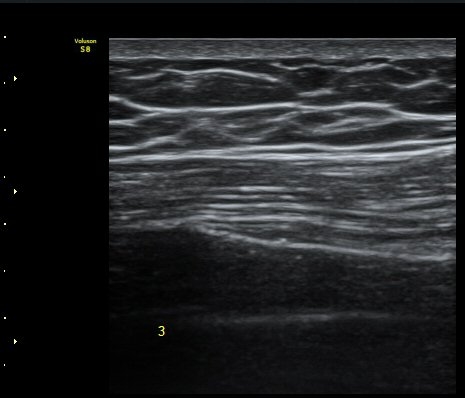

ÃÊÀ½ÆÄ °Ë»ç

¹Ì¼¼ÇÏ°Ô °¥ºñ»À ÇÇÁú°ñ ¿¬°á¼º ¼Ò½Ç°ú ¿¬ºÎÁ¶Á÷ ºÎÁ¾ÀÌ °üÂûµÊ(loss of cortical continuity and soft tissue swellingof rib)   »çÁø 1, 2, 3

3, 4,, 5 ¹øÂ° °¥ºñ»À °ñÀýÀÌ È®ÀεÊ.